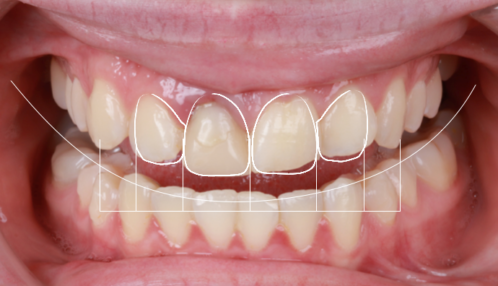

- Toma de registros fotográficos y realización de un DSD, diseño digital de sonrisa. Donde diseñamos y programamos por ordenador cómo es la sonrisa que nos gustaría para la paciente.

- Realizamos un Mock Up, o lo que es lo mismo, una prueba donde trasladamos a la boca de la paciente el diseño que hemos realizado por ordenador de cómo queremos que queden sus dientes.

Tras el tratamiento inicial esperamos 6 meses a la cicatrización final de la encia. Posteriormente realizamos un blanqueamiento radicular y una nueva reconstrucción para mejorar la estétcia. Realizamos un DSD, o lo que es lo mismo Diseño Digital de Sonrisa (Dental Smile Design) para finalizar el caso con unas carillas dentales en los 4 incisivos superiores. Realizamos el mock up para probar en boca como quedarán antes de realizarlas. Realizamos la micro-preparación de las carillas y la colocación final de las mismas.